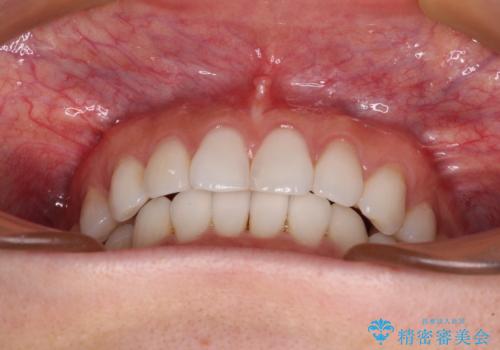

- 前歯のデコボコを気にして来院された患者様です。

海外に留学をされており、卒業後はしばらく日本にいるものの、再び就職のため出国するとのことでした。

定期的に日本に戻ってくる予定であるため、来院頻度の少ないインビザラインにて矯正治療を行うこととしました。

歯列不正が軽度であり、インビザラインの装着時間を遵守してくださったため、日本と海外を行き来しながらも2年弱でしっかりと仕上げることができました。